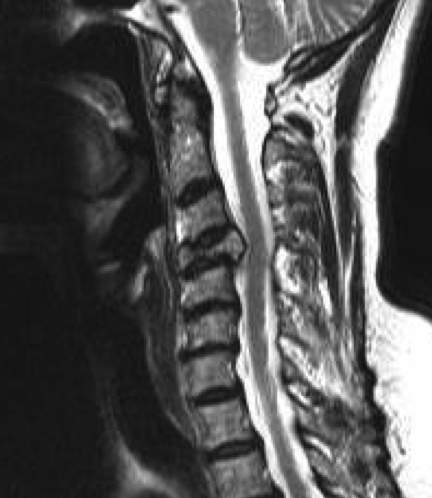

MRI

Define

- soft tissue masses

- nerve and cord impingement